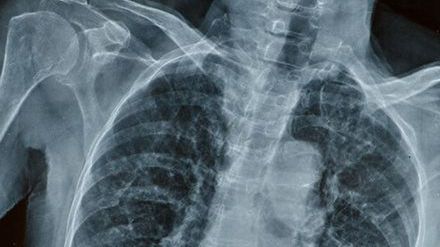

Mieszkająca w Londynie Seanie Nammock to ładna, zadbana nastolatka. Na pierwszy rzut oka nie różni się od rówieśniczek. Mało kto wie, że makijaż nakładała specjalnymi przyrządami z wydłużonymi rączkami i często sama nie potrafi się ubrać. Dziewczyna cierpi na postępujące kostniejące zapalenie mięśni (fibrodysplasia ossificans progressiva, FOP), bardzo rzadką chorobę genetyczną, która powoli zmienia jej mięśnie i ścięgna w kości.

17-latka już teraz bardzo cierpi, a dolegliwość będzie wciąż postępować. Jej ramiona są praktycznie unieruchomione. W okolicach barków wyrosła dodatkowa kość, przez co Seanie nie może podnieść rąk do góry. Nie potrafi więc nawet umyć się bez pomocy. Choroba zmienia ją w żywy posąg.

Najmniejsze uderzenie czy stłuczenie powoduje nieodwracalny wzrost kości. Dodatkowa tkanka kostna blokuje jej stawy, uniemożliwiając poruszanie się. Tymczasem dziewczyna nie może przyjmować zastrzyków, bo nawet one mogą powodować rozwój choroby. O ironio, to przede wszystkim FOP sprawia, że trudno jej unikać obrażeń. Coraz ciężej przychodzi jej sprawne poruszanie się. Prawdziwym wyzwaniem jest chociażby wejście po schodach, ponieważ trudno jej zachować równowagę. Nie może nawet pomóc sobie rękami, żeby zamortyzować potencjalny upadek.

Skany MRI i dalsze testy ukazały prawdę. – To był straszliwy szok – mówi matka Seanie. Dodaje, że od tego czasu żyje w dużym strachu o swoją córkę.

Nie ma lekarstwa na FOP. Tylko około 600 osób na świecie cierpi na tę chorobę. Przez to nie przeprowadza się na ten temat zbyt wielu badań naukowych. Seanie jest skazana na zażywanie niezliczonej ilości tabletek przeciwbólowych. Inaczej nie byłaby w stanie funkcjonować.